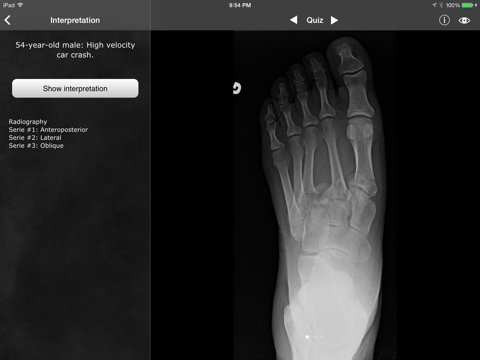

* FEATURED IN AAOS' MULTIMEDIA EDUCATION CENTER * * Now compatible with iOS 8 * RealWorld Orthopaedics is your ultimate guide to the basics of musculoskeletal medicine. This app features more than 50 chapters covering the most frequent and important diagnoses of the field, including fractures, dislocations, and degenerative diseases. The chapters are divided into sections discussing basic mechanisms of injury, diagnostic criteria and classifications, differential diagnosis as well as management. The chapters are fully illustrated using high-quality plates from Gray's Anatomy, original illustrations and original photographs. RealWorld Orthopaedics is also the best musculoskeletal radiology resource on the App Store! Not only can you see radiographs of every discussed disease, all radiologic findings can be highlighted right on the X-ray. Explore more than 150 real cases each containing: - Clinical information regarding the patient and the mechanism of injury - High-resolution X-rays - All appropriate series (anteroposterior, lateral, oblique, etc.) - Detailed radiologic interpretation - Drawings of every radiological finding right on the X-ray - Pre and postoperative controls Test your knowledge with the quiz mode, where the radiographs are presented in random order, or access a case directly either by diagnosis (e.g. Galeazzi fracture, rhumatoid artitis) or by actual radiological finding (e.g. linear hypodensity, plate and screws, irregular joint surface). By being both a radiology resource and a comprehensive clinical reference, RealWorld Orthopaedics is your must-have app for quick review on the wards, or at home. ==================================== PRAISE FOR REALWORLD ORTHOPAEDICS ==================================== "This is one of the best musculoskeletal radiology apps available. [...] Useful to any medical student, intern, or junior resident that needs to learn about musculoskeletal radiology." - TopOrthoApps.com "Highly rated orthopaedic application" - Orthopaedia.com "The ultimate iPhone app to the learning of musculoskeletal radiology" - echo-loco.fr Featured in AAOS' Multimedia Education Center (San-Francisco 2012) Featured by Apple as "New and Noteworthy" in more than 50 countries worldwide. ========================= INTERNATIONAL USER REVIEWS ========================= Great ortho app - 5 stars by miwwiw - Version 2.0.0 - Mar 21, 2012 - Australia iTunes Store Very easy to use app, best ortho app in the apple store. Great for anyone on a orthopaedic surg attachment wanting a good source of X-rays along with highlights of abnormalities plus full explanations & background info. [...] Definitely worth the $$, looking forward to future updates. --- Excellent for consenting - 5 stars by Drpsy23 - Version 2.0.0 - Apr 21, 2012 - UK iTunes Store I use this app a lot in order to inform and explain procedures to patients, Excellent to calm the anxiety of parents!!!! --- A compact, high quality atlas of skeletal radiological appearances - 5 stars by jepho - Version 1.0.0 - 31 March 2011 - UK iTunes Store A fantastic job! This is a great reference work for anyone interested in seeing real examples of diagnostic imaging for skeletal trauma and disease. The viewer is a joy to use [...] I have no hesitation in recommending this application very highly. [...] It will probably replace my battered copy of Orthopaedic Radiology (Long and Rafert) [...] This seminal work deserves to be on every clinician's iPhone. At this minimal cost, they have no excuse for not purchasing this application. I predict that it will become a classic. --- Muy buena - 5 stars by Unpg - Version 2.0.0 - Feb 24, 2012 - Spain iTunes Store Excelente y necesaria para traumas